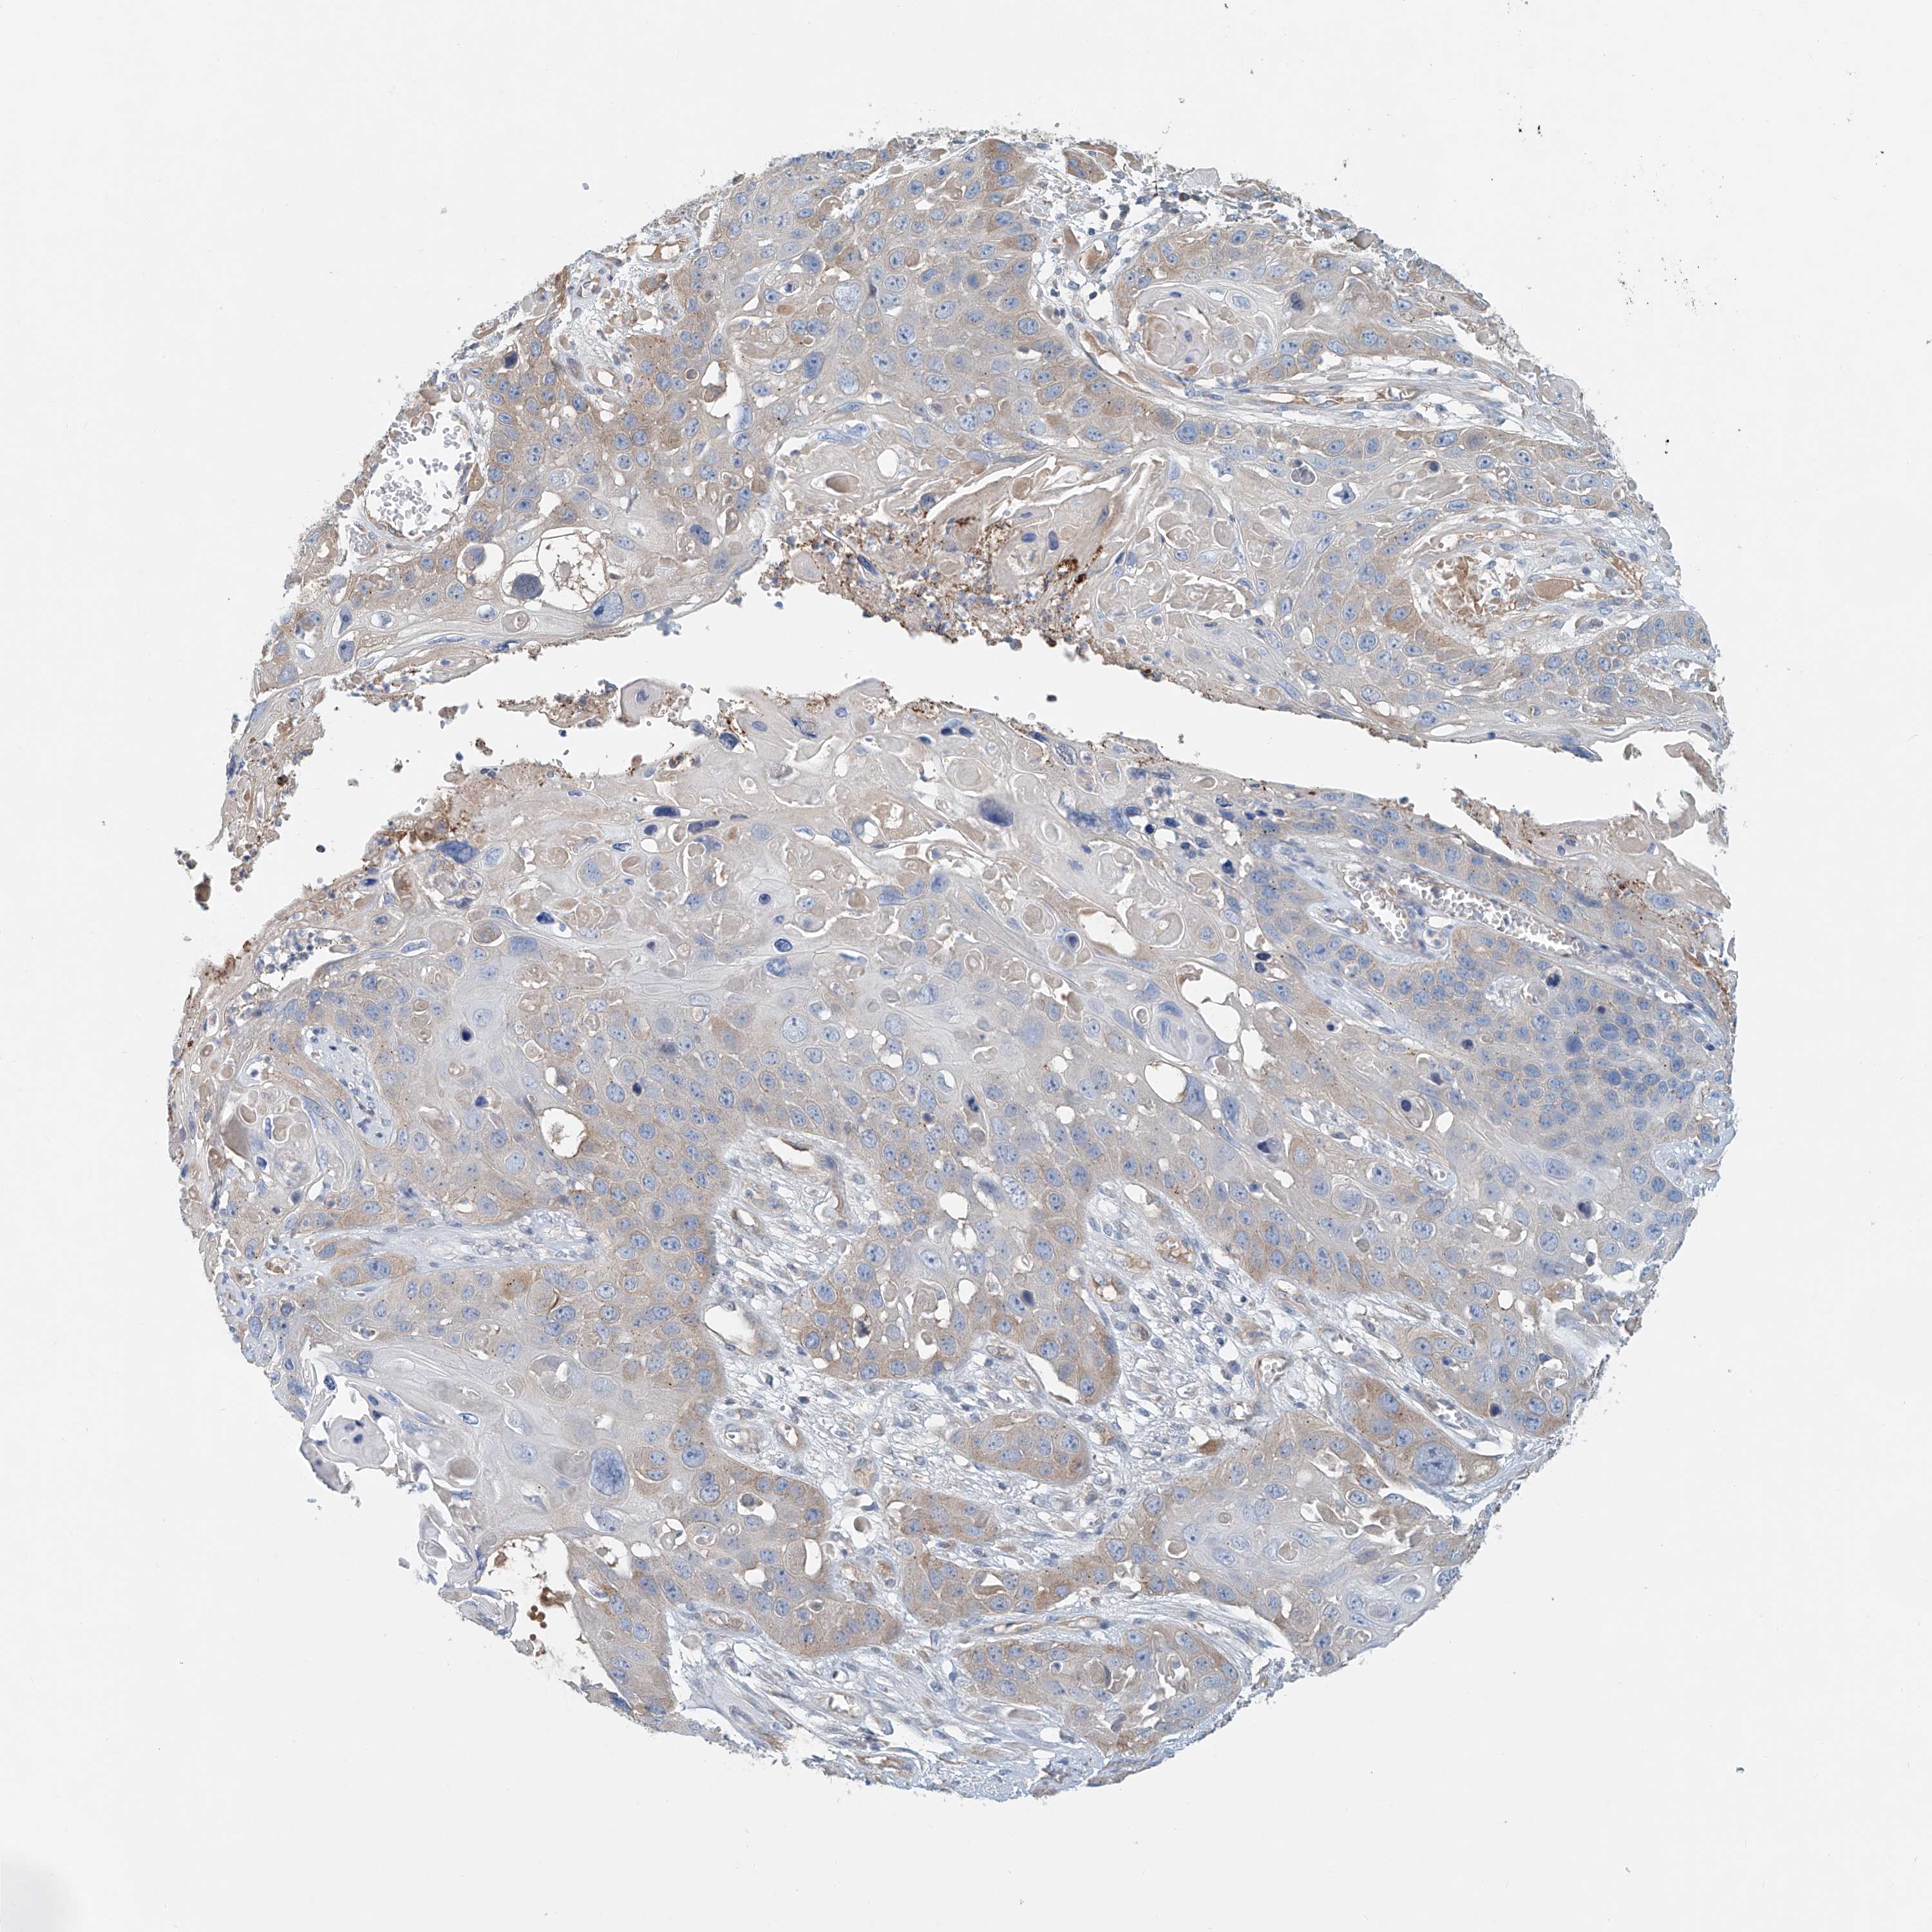

Basal cell and squamous cell cancer

SKIN CANCER - Protein expressioni

A mouse-over function shows sample information and annotation data. Click on an image to view it in a full screen mode. Samples can be filtered based on level of antibody staining by selecting one or several of the following categories: high, medium, low and not detected. The assay and annotation is described here.

Antibody stainingi

Antibody staining in the annotated cell types in the current human tissue is reported as not detected, low, medium, or high, based on conventional immunohistochemistry profiling in selected tissues. This score is based on the combination of the staining intensity and fraction of stained cells.

Each image is clickable and will lead to virtual microscopy that enables deeper exploration of all samples and also displays staining intensity scores, fraction scores and subcellular localization as well as patient and tissue information for each sample.

Antibody HPA031106

Antibody HPA031107

Staining

High

Medium

Low

Not detected

Intensity

Strong

Moderate

Weak

Negative

Quantity

>75%

75%-25%

<25%

None

Location

Nuclear

Cytoplasmic/membranous

Cytoplasmic/membranous,nuclear

Squamous cell carcinoma, metastatic, NOS

Squamous cell carcinoma, NOS